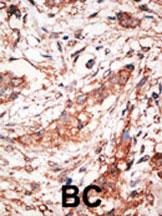

Formalin-fixed and paraffin-embedded human cancer tissue reacted with the primary antibody, which was peroxidase-conjugated to the secondary antibody, followed by DAB staining. This data demonstrates the use of this antibody for immunohistochemistry; clinical relevance has not been evaluated. BC = breast carcinoma; HC = hepatocarcinoma. |